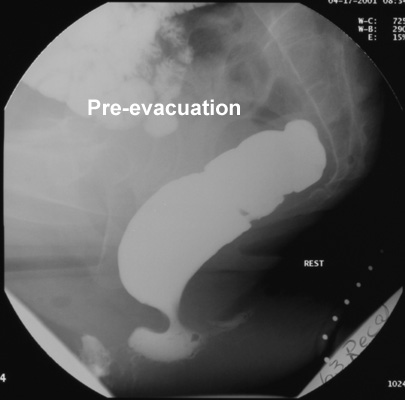

Rectocele

- A rectocele is a forward out-pouching of the anterior rectal wall

which occurs during defecation or straining.

- It occurs much more frequently in females, probably because of the

compliance of the rectovaginal septum.

- During evacuation, part of the contrast material may be

sequestered in this pseudodiverticulum, and full rectal emptying may

not be achieved at the first attempt.